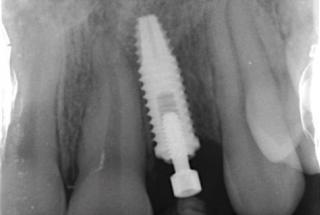

Clinical cases

MPI closely monitors clinical cases in the market to ensure their correct functioning and successful outcome.